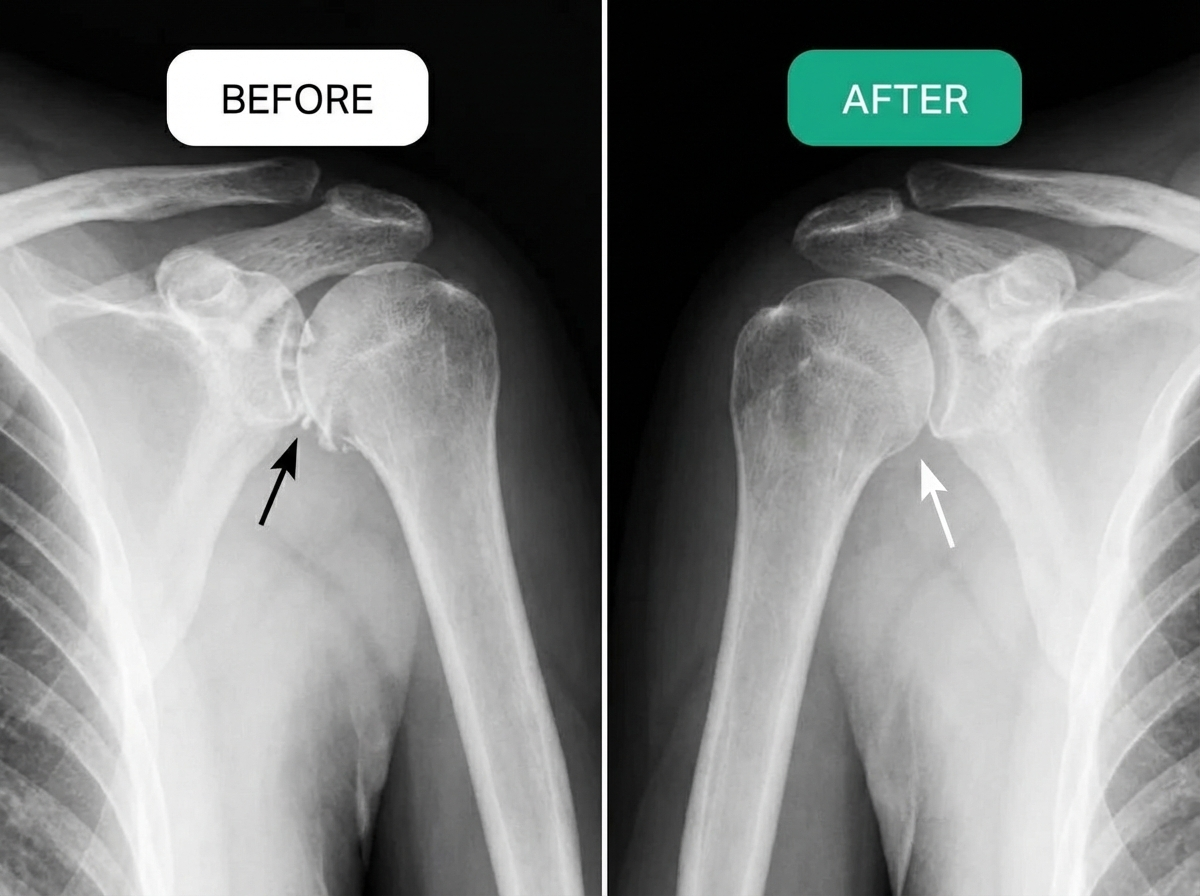

THE REAL ROOT CAUSE OF ROTATOR CUFF PAIN

Think of your shoulder like a door hinge.

When you're younger, it moves smoothly — quiet, fluid, effortless.

That’s because healthy tissue is supported by steady blood flow. Oxygen and nutrients reach the muscles, tendons and joint structures efficiently, allowing them to repair and recover.

But as we age, circulation naturally slows.

Small blood vessels become less efficient. Recovery takes longer.

Inflammation lingers.

And gradually, movement doesn’t feel as smooth as it once did.

Instead of gliding, it begins to catch.

Instead of flowing, it stiffens.

You feel it first thing in the morning.

It’s not just “wear and tear.”

In many persistent cases, it’s reduced tissue support.

When blood flow declines, healing slows.

When oxygen delivery drops, recovery weakens.

Over time, the joint becomes more reactive, more sensitive, more prone to ongoing discomfort.